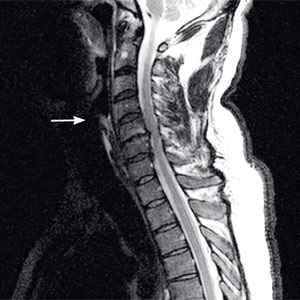

Остеохондроз шейного отдела позвоночника — очень часто встречающаяся патология. При резких движениях это состояние провоцирует головокружение.=

Случаются головокружения и при таком широко распространённом заболевании, как остеохондроз шейного отдела позвоночника, особенно при резких и неловких движениях. Такие головокружения кратковременны. Они могут сопровождаться нарушением равновесия, лёгким пошатыванием. Их главная причина — раздражение нервного сплетения, мышц и связок шеи.